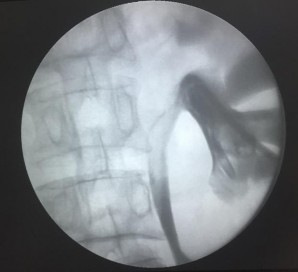

Bơm khoảng 20ml thuốc cản quang vào bể thận để kiểm tra vị trí ống dẫn lưu Pigtail 8F.

Hình 2.23. Kiểm tra vị trí ống dẫn lưu Pigtail 8F

(Nguồn: chụp tại Bệnh Viện Trường Đại Học Y - Dược Huế)